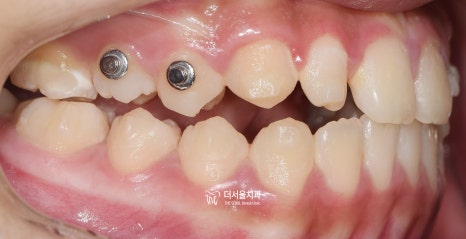

『페이스 마스크(face mask) 사용』

착용 전

착용 후

악궁 확장장치와 페이스마스크를 사용했습니다.

요즘은 잘 안 쓰죠?

구외장치도 같이 껴야 되기 때문에

심미성이 떨어지면서, 아이들이 싫어합니다.

왜냐하면 친구들이 많이 놀리고,

하루에 대다수 시간을 끼고 있어야

효과를 볼 수 있기 때문이죠.

(이때는 인비절라인 퍼스트가 없었습니다.)